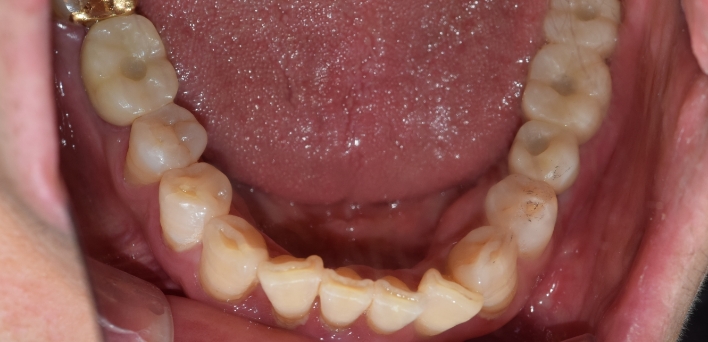

임플란트 : 손 ** 님 (50대)

After After

2020.02.30

※ 더서울치과의원은 의료법을 준수하며 위 케이스는 실제 환자의 동의를 얻은 사례로 치료 전, 후가 동일한 환경에서 촬영되었습니다.

환자 케이스에 따라 부작용이 발생할 수 있습니다. 이 부분은 의료진의 충분한 상담과 체크를 통해 예방하고 줄일 수 있습니다.

[임플란트 부작용] 수술 후 관리가 소홀할 경우 출혈, 주위염 등의 부작용이 발생할 수 있어 구강 위생을 철저히 유지하고, 정기적인 검진을 통해 상태를 점검하는 것이 중요합니다.

위, 아래 6개씩 식립

디지털 풀아치 임플란트

임플란트 Before & After